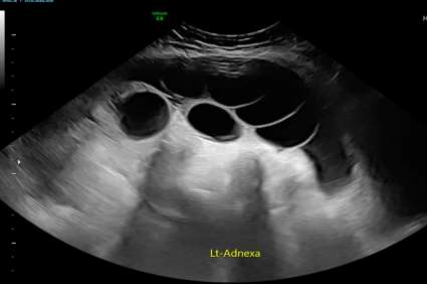

The patient was admitted under the care of the gynaecology team and provided with pain relief and hydration. A pelvic ultrasound was scheduled, but the extreme pain precluded a transvaginal examination. A transabdominal ultrasound revealed bilateral enlarged ovaries with multiple cysts of varying sizes, mild internal vascularity, and the following dimensions: right ovary 12 × 12 × 10 cm and left ovary 23 × 18 × 9 cm. Moderate free fluid was detected within the pouch of Douglas, with a depth of 10.7 cm. The appearance of ovaries corresponded with ovarian hyperstimulation syndrome.

Figure 1